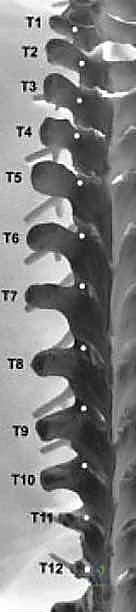

1. السويقات الصدرية (T1-T12):

* الحجم والشكل: تكون أصغر حجماً وأكثر بيضاوية مقارنة بالسويقات القطنية. تكون أضيق ما يمكن في البعد الإنسي الوحشي (من الداخل للخارج)، خاصة في منطقة الصدر الوسطى (من T3 إلى T5). يزداد عرضها تدريجياً كلما اتجهنا لأعلى نحو الرقبة أو لأسفل نحو أسفل الظهر.

* المخاطر العصبية الوعائية (Neurovascular Risks): في منطقة العمود الفقري الصدري، يقع الحبل الشوكي مباشرةً في مسار المسمار إذا تم توجيهه بشكل خاطئ. من الناحية الجانبية، توجد الحزم العصبية الوعائية الوربية (Intercostal nerves and vessels). أما من الناحية الأمامية، فإن الشريان الأورطي النازل (خاصة على الجانب الأيسر) والوريد الفرد (Azygos vein على الجانب الأيمن) يمثلان قلقًا جراحياً كبيراً. أي اختراق إنسي (باتجاه الداخل للقناة الشوكية) يمكن أن يؤدي إلى إصابة عصبية كارثية للحبل الشوكي، بينما الاختراق الأمامي لجسم الفقرة يمكن أن يؤدي إلى مضاعفات وعائية مميتة.

2. السويقات القطنية (L1-L5):

* الحجم والشكل: أوسع بكثير وأكثر قوة وصلابة من السويقات الصدرية، مما يجعلها مثالية لتثبيت المسامير الكبيرة. يميل العرض إلى الازدياد كلما اتجهنا لأسفل (الفقرة L5 تمتلك أوسع سويقات).

* المخاطر العصبية الوعائية: في هذه المنطقة، ينتهي الحبل الشوكي (عادة عند L1/L2) وتبدأ حزمة من جذور الأعصاب تسمى "ذيل الفرس" (Cauda Equina). تحتوي السويقات القطنية على جذور الأعصاب الخارجة أسفلها مباشرة. أي اختراق إنسي للمسمار يمكن أن يصيب أعصاب ذيل الفرس أو جذر العصب العابر. الاختراق الجانبي أو السفلي يمكن أن يصيب جذر العصب الخارج. أماميًا، تقع الأوعية الدموية الكبرى (الشريان الأورطي والوريد الأجوف السفلي) مباشرةً أمام أجسام الفقرات.

3. السويقات العجزية (S1):

* الحجم: سويقة الفقرة العجزية الأولى (S1) هي الأوسع والأضخم بين جميع السويقات، مما يوفر نقطة تثبيت قوية جداً لقاعدة البناء الجراحي.

* المخاطر: التوجيه الدقيق مطلوب لتجنب اختراق المفصل العجزي الحرقفي أو إصابة الأعصاب العجزية.